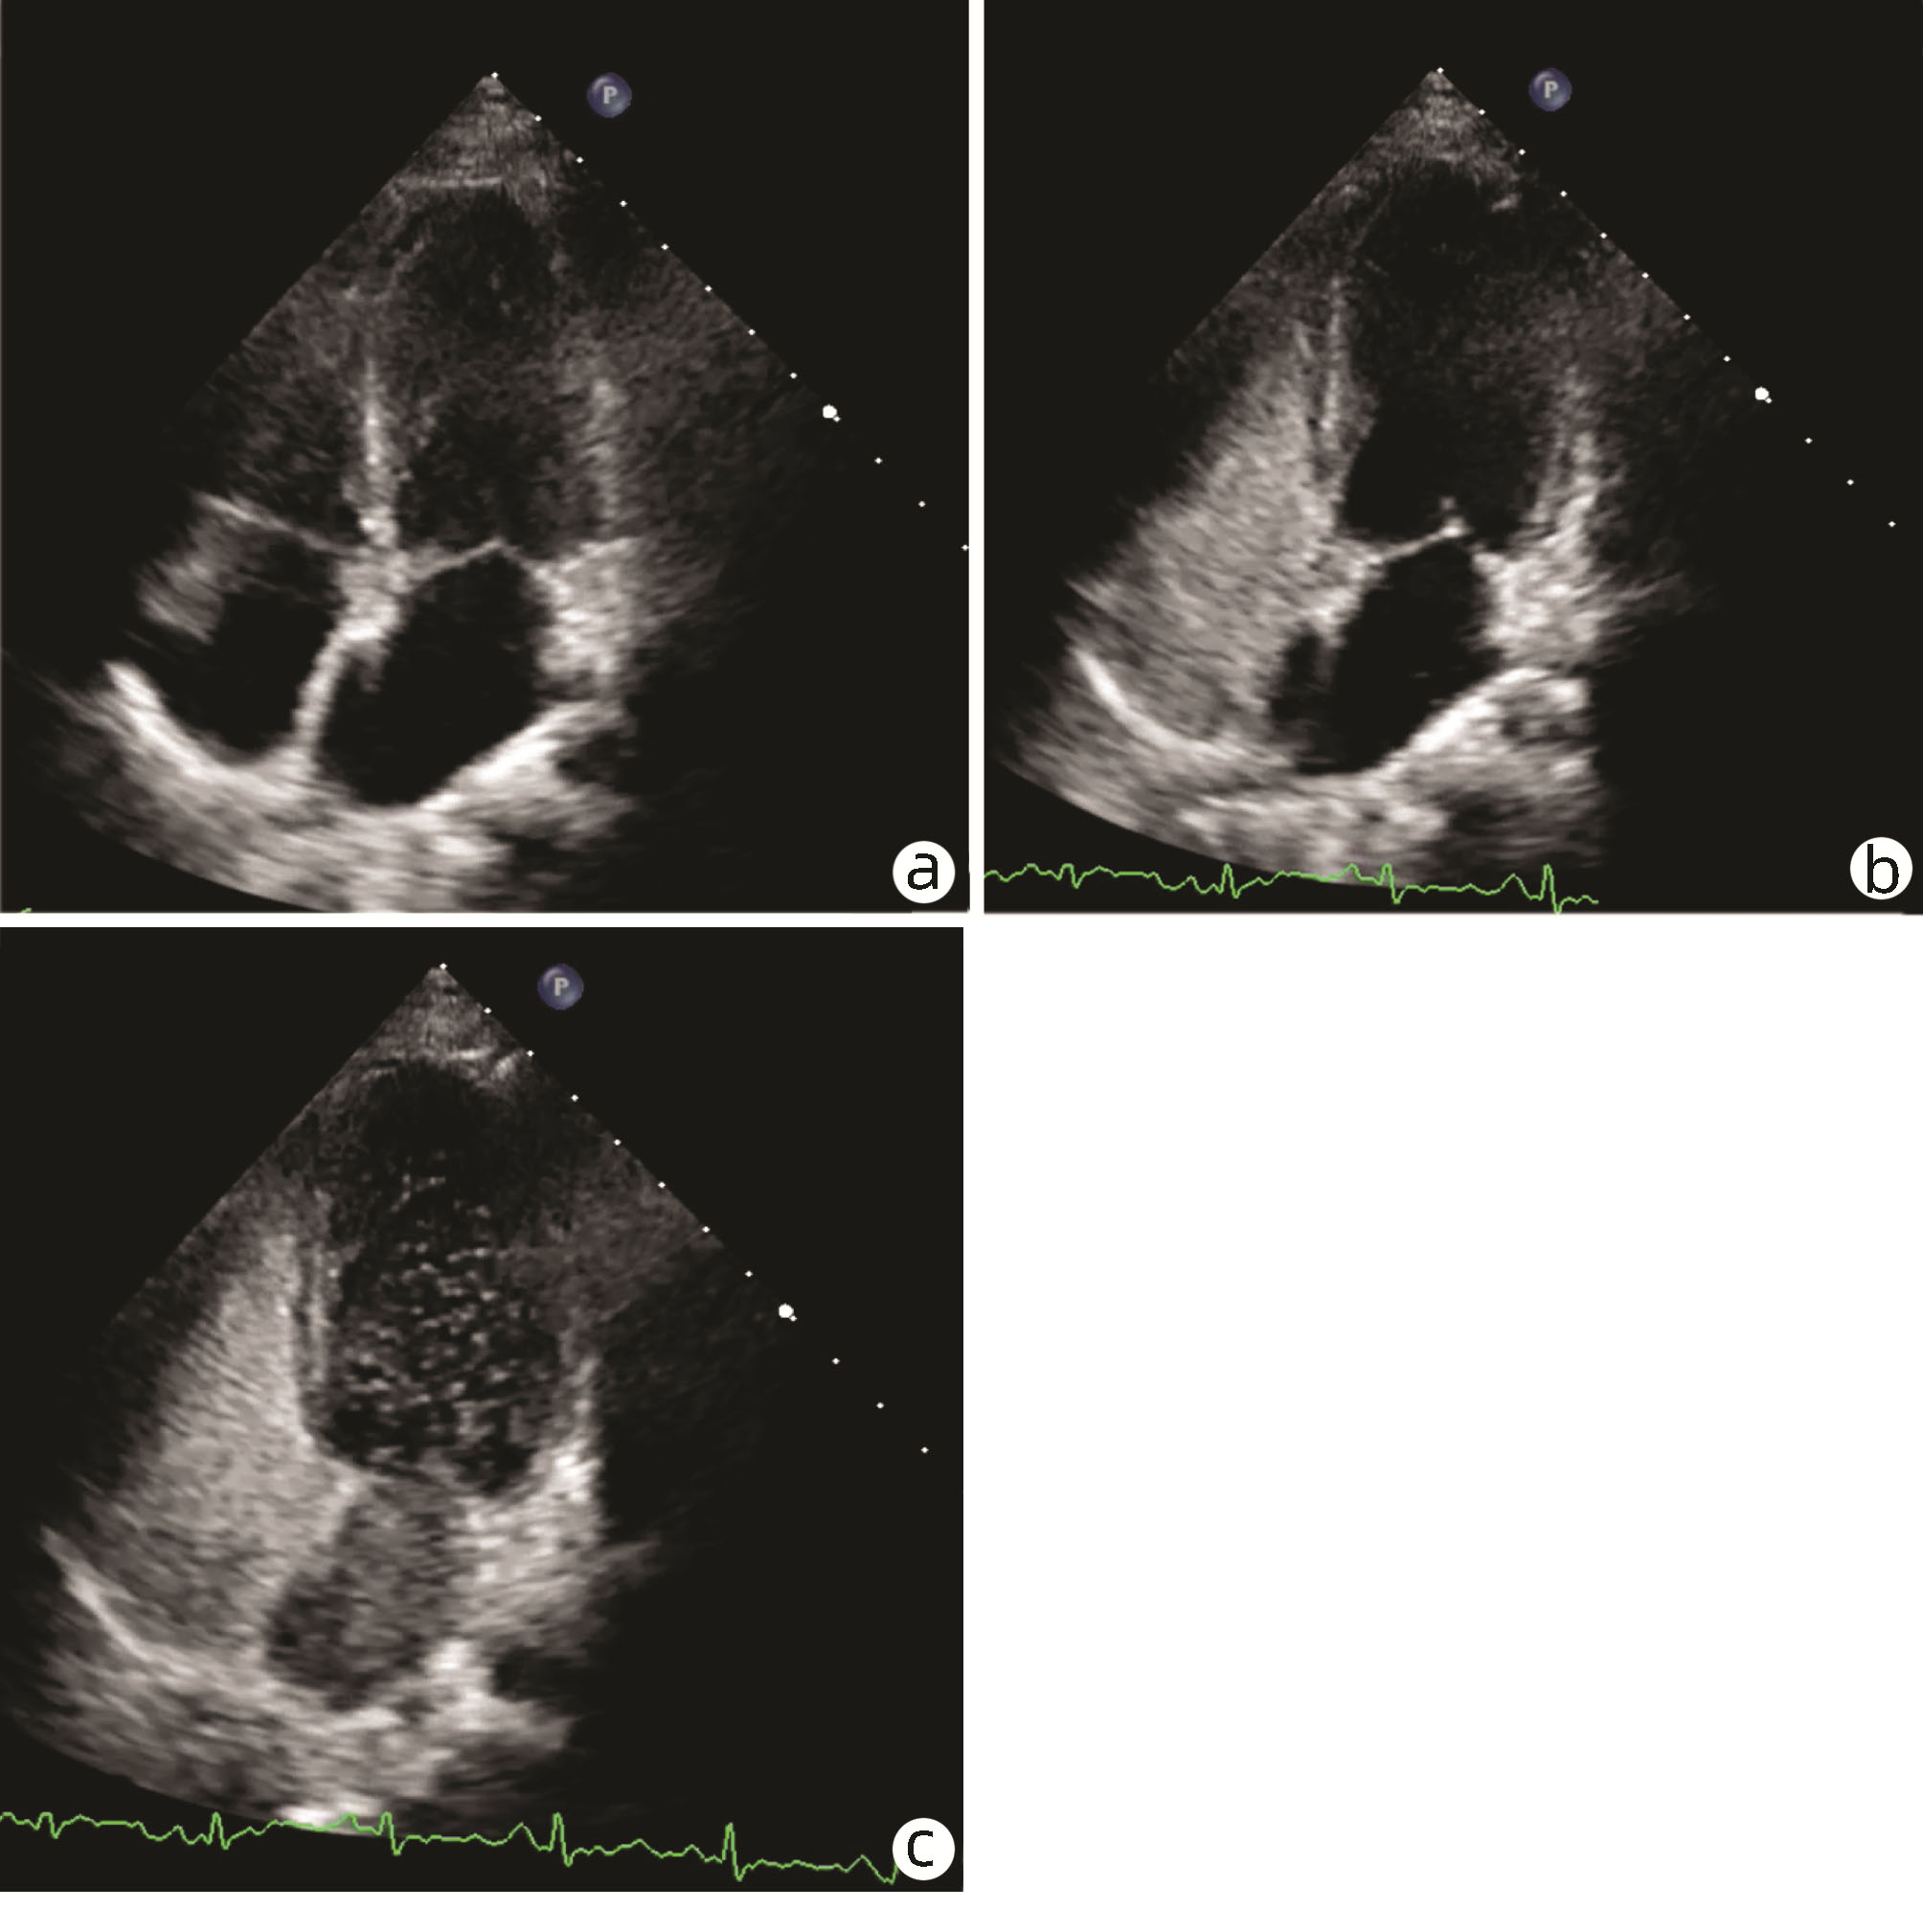

Hepatopulmonary syndrome after craniopharyngioma operation in children: A case report

Figures(3)  / Tables(2)